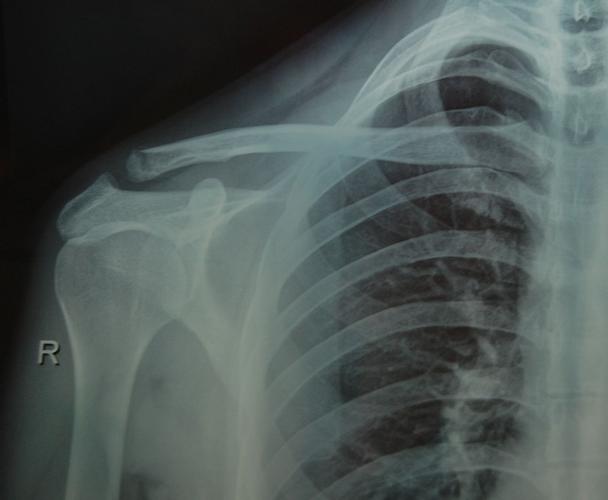

肩部正常x片图片

肩部正常x片图片,正常的肩关节x片图片

肩关节正位-x线图

求助,各位老师看看是否肩锁关节脱位?

3月初骑车跌伤,导致右肩锁骨远端骨折,4月底拍x片右肩

正常的肩关节x片图片

正常人肩部x光片